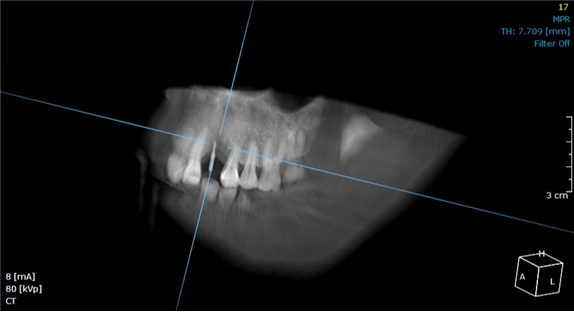

이후 CT 촬영을 통해 식립 위치와 각도가 정확한지 파악하여 안전하게 수술이 진행되었습니다. CT 촬영 결과에 따라 필요한 경우 가이드 핀의 위치와 각도를 수정하여 만족스러운 결과를 얻을 수 있습니다.